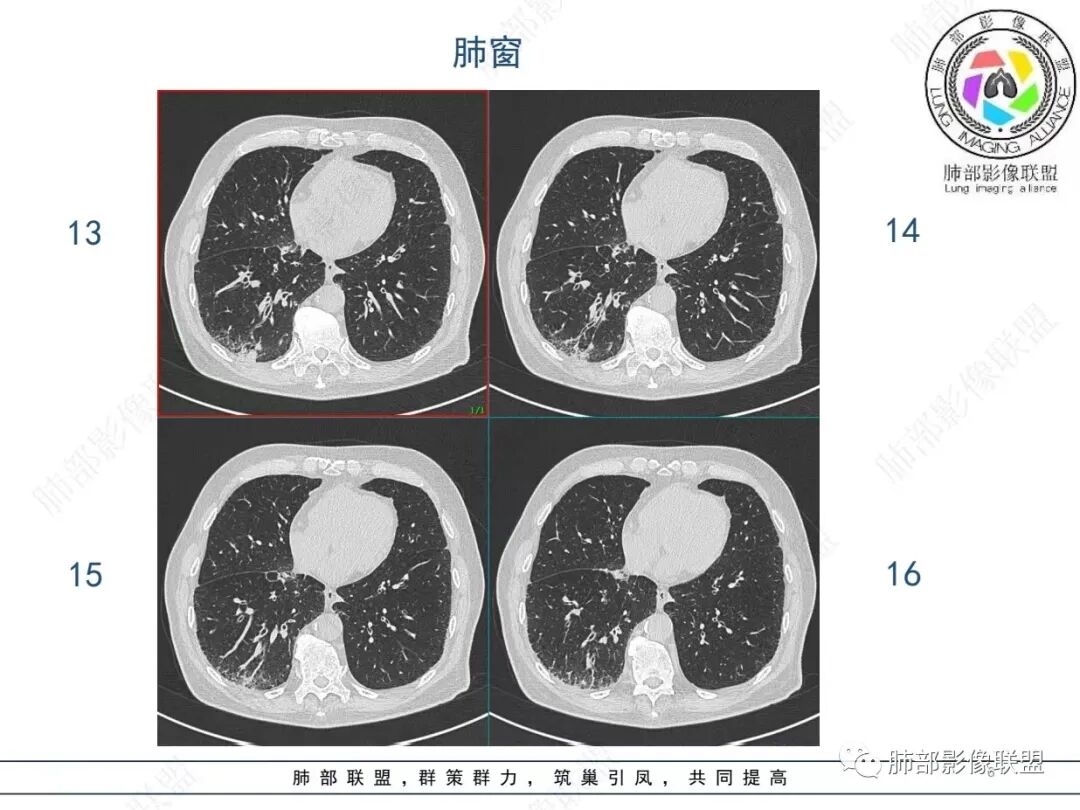

老年男性,发作性气喘,实验室检查白细胞增高。肺部影像表现:右肺胸膜下占位性病变,肺气肿背景,内部可见空腔/空泡影,周围可见小结节,增强动脉期明显强化,静脉期及延迟期强化减低,右侧肺门可见肿大淋巴结,有吸烟史,近年减少,首先考虑恶性肿瘤,肺小细胞癌/鳞癌,隐球菌作为鉴别诊断,病例穿刺活检。

老年男性,气短,胸痛半年,考虑慢性病史,无发热,常见的肺部感染可以排除,右肺下叶基地段靠近胸膜实变影,边缘清楚,不均匀强化,可见空泡征,点状血管影,周围小叶中央型结节,有网格影,支气管扩张,磨玻璃影,肺间质改变,右侧肺门淋巴结肿大,综合考虑恶性肿瘤并肺内转移

老年男性,胸疼入院,影像表现,右肺下叶胸膜下结节,边界清晰,与支气管关系不密切,病灶内见空洞?增强病灶均匀强化,右肺门可见增大淋巴结,考虑恶性病变,小细胞癌,其次鳞癌

老年男性,肺气肿背景,右肺下叶,右肺下叶胸膜处实性结节,形似山丘,有分叶,病灶内可见扩张细支气管/空泡,边缘可见弯曲血管,增强后不均匀强化,可见血管影,病灶胸膜侧呈小波浪??状,局部突入胸膜面,右肺门肿大淋巴结。考虑恶性结节,小细胞肺癌,腺癌,鉴别炎性肉芽肿。建议ct下穿刺活检。

老年男性,肺气肿病史,支气管束增粗,管壁增厚,右肺下叶后基底段胸膜下肿块,土豆征,边界清,有膨隆,小支气管边缘阻断,见集血管束征,肿块强化明显(快进快出特点),并偏心空洞,胸膜下栽赃,周围肺结构破坏(蜂窝状影表现),右肺门淋巴结转移肿大,血管内皮生长因子偏高,肿块与小支气管,血管束关系密切,强化特点,定恶性肺肿瘤,小细胞Ca。

老年男性,肺气肿,右肺下叶胸膜下结节,边缘毛躁,周围多发间质增厚,临近胸膜下脂肪间隙模糊,增强后动脉期不均匀强化,延迟期强化较低,右肺门肿大淋巴结,考虑恶性,鳞癌,小细胞肺癌,鉴别炎性肉芽肿性结节

右肺下叶胸膜下结节,边界清,边缘平直膨隆,血管集束,其内空洞,明显不均匀强化,考虑腺癌?小细胞癌?鉴别隐球菌

肺气肿,胸膜下结节,边界清晰,边缘毛糙,病灶内见空洞,增强病灶均匀强化,右肺门可见增大淋巴结,考虑恶性病变,小细胞癌,其次鳞癌,鉴别隐球

老年男性,肺气肿背景,右肺下叶胸膜下团块影,明显强化,其内空泡征,周边血管聚集,右肺门淋巴结增大,考虑腺癌?

右下叶胸膜下结节,宽基底与胸膜相连,结节与胸膜相交呈钝角〈山丘征〉,内可见充气扩张的支气管,中度强化,结节边缘无毛刺,内见走行自然的血管影,提示破坏力及收缩力差,右肺门可见肿大淋巴结,老年烟民,考虑恶性占位,支持小细胞癌

右肺下叶胸膜下结节,呈山丘状,生长在慢支肺气肿间质纤维化的基础上,边缘相对光滑清晰,右肺门淋巴结肿大,强化呈速升速降,老年男性,吸烟史,考虑小细胞肺癌,鉴别隐球

老年男性,吸烟史40年,肺气肿背景,胸膜下结节,边缘膨隆,增强后结节内有片状坏死区,右肺门及纵隔肿大淋巴结,考虑恶性,鳞癌?小细胞代排

老年患者,右下肺胸膜下结节,有血管聚集、空泡征,强化明显,右肺门见肿大淋巴结。考虑腺癌,鉴别肉芽肿性病变

老年男性,长期抽烟病史,右下肺胸膜下结节,有分叶,胸膜下栽桩,肿块增强可见明显不均匀强化,考虑恶性,鳞癌可能性大,鉴别小细胞肺癌。

男,80,发作性气喘半年,加重1天。长年大量吸烟史。肺部CT:肺气肿背景,右肺胸膜下实性占位,处于外周大疱带与气肿带交界,山丘征,边缘膨隆,边界较清,血管集束,周围可见小结节。增强不均匀强化,内可见迂曲模糊血管影,右肺门、隆突下可见肿大淋巴结。首先考虑恶性肿瘤,小?鳞?鉴别PC、TB等。